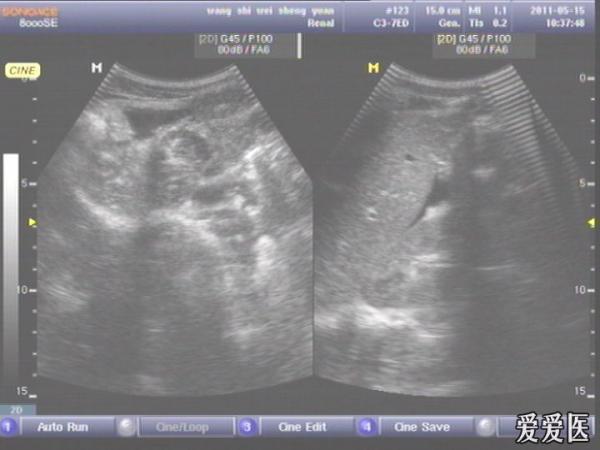

患者,男,38岁,进食后突发上腹部持续性剧烈疼痛一小时来查。超声见横膈与肝之间、上腹部皮下气体强反射回声,后伴多重反射,肝前、肝肾间隙,腹腔肠管间均可见游离无回声区。直视腹部见上腹部似板样。结合病史提示“胃肠道穿孔”。急诊手术证实。

左肝外叶的那个切面如果能看到气体回声的话,那就应该高度怀疑这个病了。好切面,好好学习,太有用了,楼主辛苦感谢感谢。